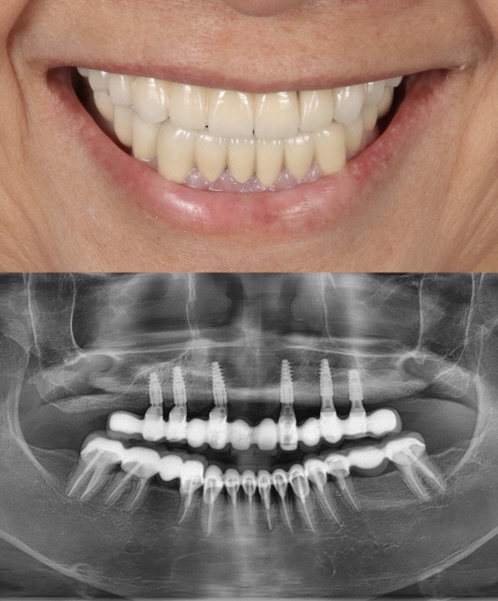

Before

After

ALL-ON-4

This patient transitioned from a removable denture to a fixed full-arch prosthesis using the All-on-4 technique. With strategically placed implants and immediate loading, a new confident smile was delivered within a single day. Work done by our expert team at Moral Dental Clinic